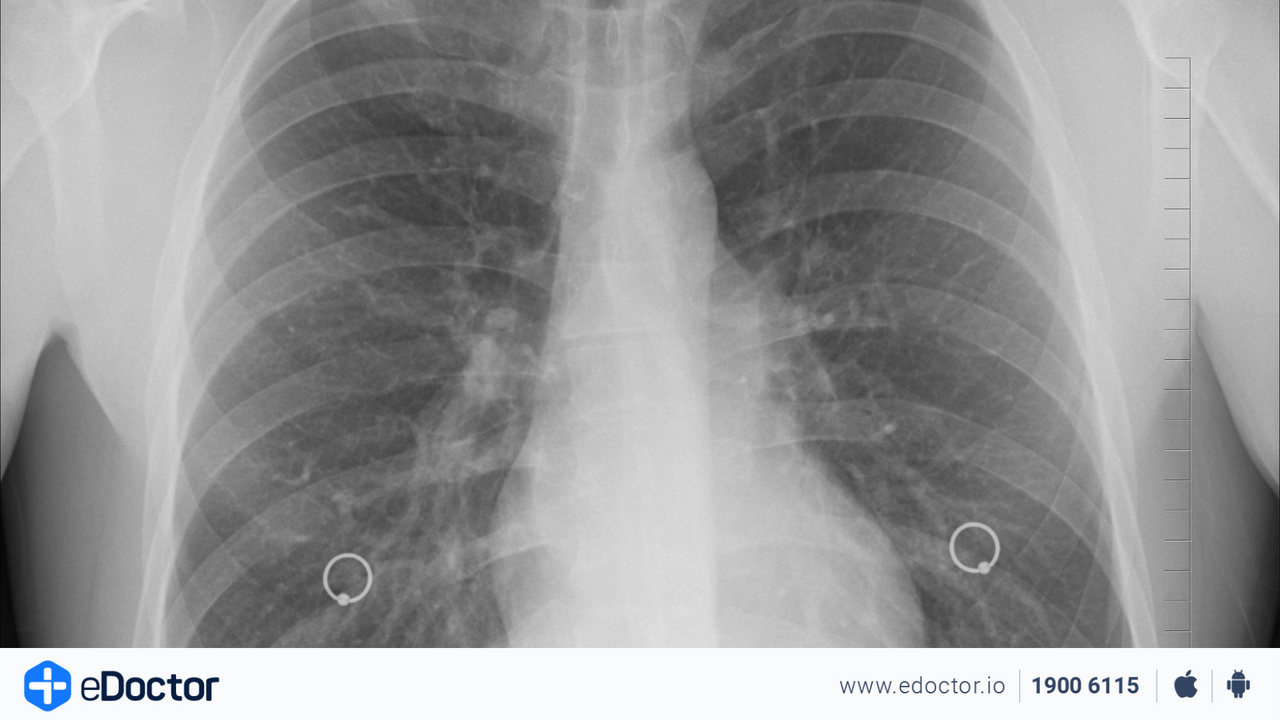

Hen suyễn: Theo Tổ chức Y tế Thế giới (WHO), hen suyễn là căn bệnh mạn tính do viêm và hẹp đường thở, có thể gây ra cảm giác tức ngực, khó thở, thở khò khè và ho. Các nhà nghiên cứu phát hiện ô nhiễm không khí có thể làm trầm trọng thêm các triệu chứng hen suyễn và cũng là nguyên nhân khiến số người mắc bệnh này ngày càng tăng. Khí ozone, chất gây ô nhiễm ngoài trời phổ biến, có thể là tác nhân gây hen suyễn và kích thích phổi hoặc đường thở. Ảnh: Chestnet.